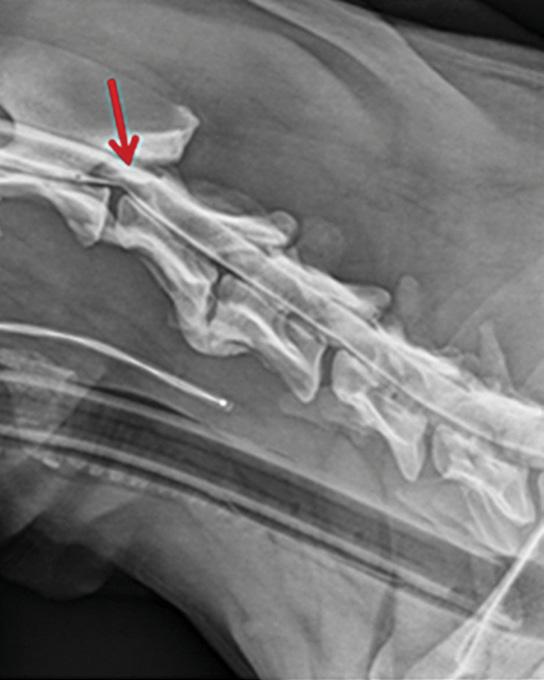

The Fourakers took Cuda to the Center for Veterinary Specialty Care in Fort Worth, where he underwent an MRI. Veterinarians found a cyst on top of the spinal cord between the second and third cervical vertebrae. Veterinarians told the Fourakers surgery was the only option. It would be a delicate procedure with significant risks and an unknown longterm prognosis.

Based on findings of an MRI, OSU anesthetized Cuda and performed tests suggesting the dog’s condition was complicated by additional abnormalities in the cervical vertebrae that may cause future problems.

In May, Cuda underwent a laminectomy and Rochat removed the cyst.

arrows identify the lesion on cuda’s spinal cord.